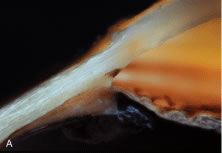

The Uveal and Corneoscleral Meshwork The uveal meshwork is composed of branching and anastomosing cord-like beams (Fig. 22). Thecores of these beams are composed of collagen and elastin that are enveloped in a continuous wrapping of thin endothelial cells that are capable of removing particulates from the flow pathways by phagocytosis29 (Fig. 23). Phagocytosis would seem to be at some long-term cost to the meshwork. As in the corneal endothelium, mitotic rates are inadequate to fully replenish this population, resulting in an age-related loss of endothelial cells.30 Whether this progressive loss contributes to the development of glaucoma remains uncertain.31,32 Clearly in the uveal meshwork there are ample open spaces for aqueous flow. As one progresses deeper into the meshwork, however, the spaces become progressively smaller (see Fig. 23). As such, in the corneoscleral meshwork, the appearance is more aptly described as perforated sheets. The basic structure of the corneoscleral meshwork is similar to that seen in the uveal meshwork. A central core of collagen and elastic fibers is enveloped in a thin endothelial wrapping. The Juxtacanalicular Region The portion of the trabecular meshwork between the corneoscleral beams and the inner wall of Schlemm's canal has a fundamentally different structure. Instead of connective tissue beams confined within endothelial wrappings, the juxtacanalicular (JCT) region is an open connective tissue matrix in which fibroblast-like cells, rather than endothelial cells, are found (Fig. 24). In addition, detailed ultrastructural studies have documented that tendons from the longitudinal bundle of the ciliary muscle extend into the meshwork, culminating in a system of elastic fibers that connect to the inner wall of Schlemm's canal, called the cribriform plexus33 (Fig. 25A and B). It is within this connective tissue matrix of the JCT region that most of the resistance to aqueous outflow is held to reside, but the actual source of this resistance has remained elusive.34 For years, it was assumed that the apparently open spaces of the trabecular meshwork were filled completely with a glycosaminoglycan gel, composed principally of hyaluronic acid.35 The natural extension of this argument was that an age-related increase in this material occurred, increasing the resistance further and resulting in the elevated pressure that characterizes primary open-angle glaucoma (POAG). In the past few years, however, it has been possible to histochemically localize hyaluronan, and it is now clear that most of the open spaces in the uveal and corneoscleral regions of the trabecular meshwork are not filled with a gel (Fig. 26A). Some hyaluronan is found in the JCT region, but it appears that the amount decreases with age (see Fig. 26B) and decreases even further in POAG, raising doubts regarding the long-held theory explaining the increased resistance in POAG.36–38 SCHLEMM'S CANAL From the JCT region, aqueous humor must traverse the continuous endothelial lining of Schlemm's canal to enter its lumen. How aqueous humor traverses the endothelium of Schlemm's canal remains one of the enigmatic problems of ocular anatomy and physiology. The wall of the Schlemm's canal closest to the anterior chamber, called the inner wall of Schlemm's canal, manifests unusual, large vacuolar structures called giant vacuoles (Fig. 27). These vacuoles appear to be pressure dependent and are not found unless the inner wall is fixed under conditions of flow.39 Although opinion is not unanimous, the most popular theory is that aqueous traverses the inner wall of Schlemm's canal though tiny openings induced to form within the walls of these vacuoles, called pores40 (Figs. 27 and 28 ). The process appears to be pressure dependent but energy independent. THE FLOW PATHWAYS BEYOND SCHLEMM'S CANAL Approximately 30 external collector channels lead from the outer wall of Schlemm's canal toward the surface of the sclera. External collector channels have been shown to exhibit smooth muscle actin implying that these vessels could constrict and in doing so regulate outflow.41 But, the contribution of this portion of the outflow pathway to overall resistance is presumed to be small. Grant removed the entire trabecular meshwork and opened the anterior chamber to Schlemm's canal. Under these circumstances, 75% of the resistance to outflow was removed.42 From the external collector channels aqueous passes into a tortuous system of passages called the deep scleral plexus that lead in turn to the deep scleral veins and finally to the episcleral veins (Fig. 29). Through this tortuous route the aqueous and blood are mixed. But a smaller number of unique vessels called aqueous veins (of Ascher) bypass this tortuous pathway and connect directly to the episcleral veins.43 Although their significance remains unknown, these unique vessels are readily identified clinically near the limbus because the aqueous humor and blood within them have yet to mix. In these vessels a central clear stream of aqueous is bordered on either side by slower streams of blood. |